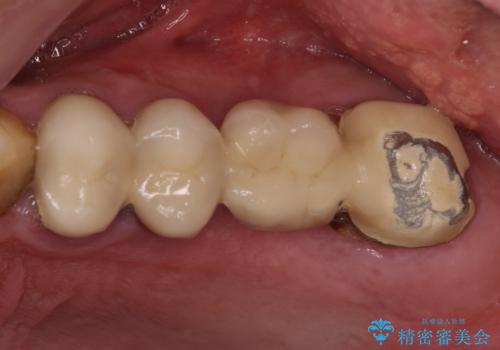

- 咬んだときに奥歯に痛みを感じるとのことで来院された患者様です。

診査の結果、左側は奥歯2本、右側は1本の抜歯が必要であることが分かりました。

抜歯となった歯は全て神経が抜かれた歯であり、強大な咬合力によって破折したことが原因で抜歯となりました。